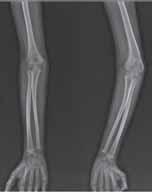

Przebieg szczeliny złamania: A – złamanie poprzeczne (RTG, widok z przodu); B – złamanie skośne (RTG, widok z przodu i z boku); C – złamanie spiralne (RTG, widok z przodu i z boku); D – złamanie w kształcie motyla (RTG, widok z boku); E – złamanie wieloodłamowe (RTG, widok z przodu i z boku).